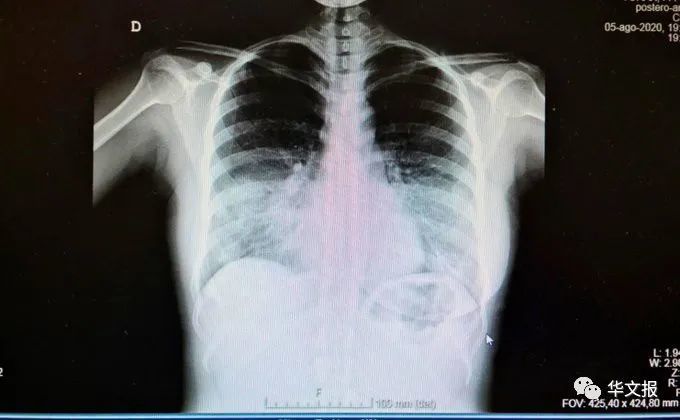

【新冠病毒|医生发出警报:二次爆发已经开始,病毒又回来了!而大家好像什么也不担心!】Pascual Pi era在文中讽刺地写道:“就在这里!!!他们回来了!”在Twitter帖子的旁边 , 还附上了一张肺部的X射线照片 , 中下部为白色 。 当被问及X射线的含义时 , Pi era回答说:“正常情况下 , 肺部是射线可透的 。 在X射线中应该是完全黑色的 。 而在这两个肺部的底部看起来都是半透明的 , 这说明新冠病毒已经严重感染到了肺部 。 ”